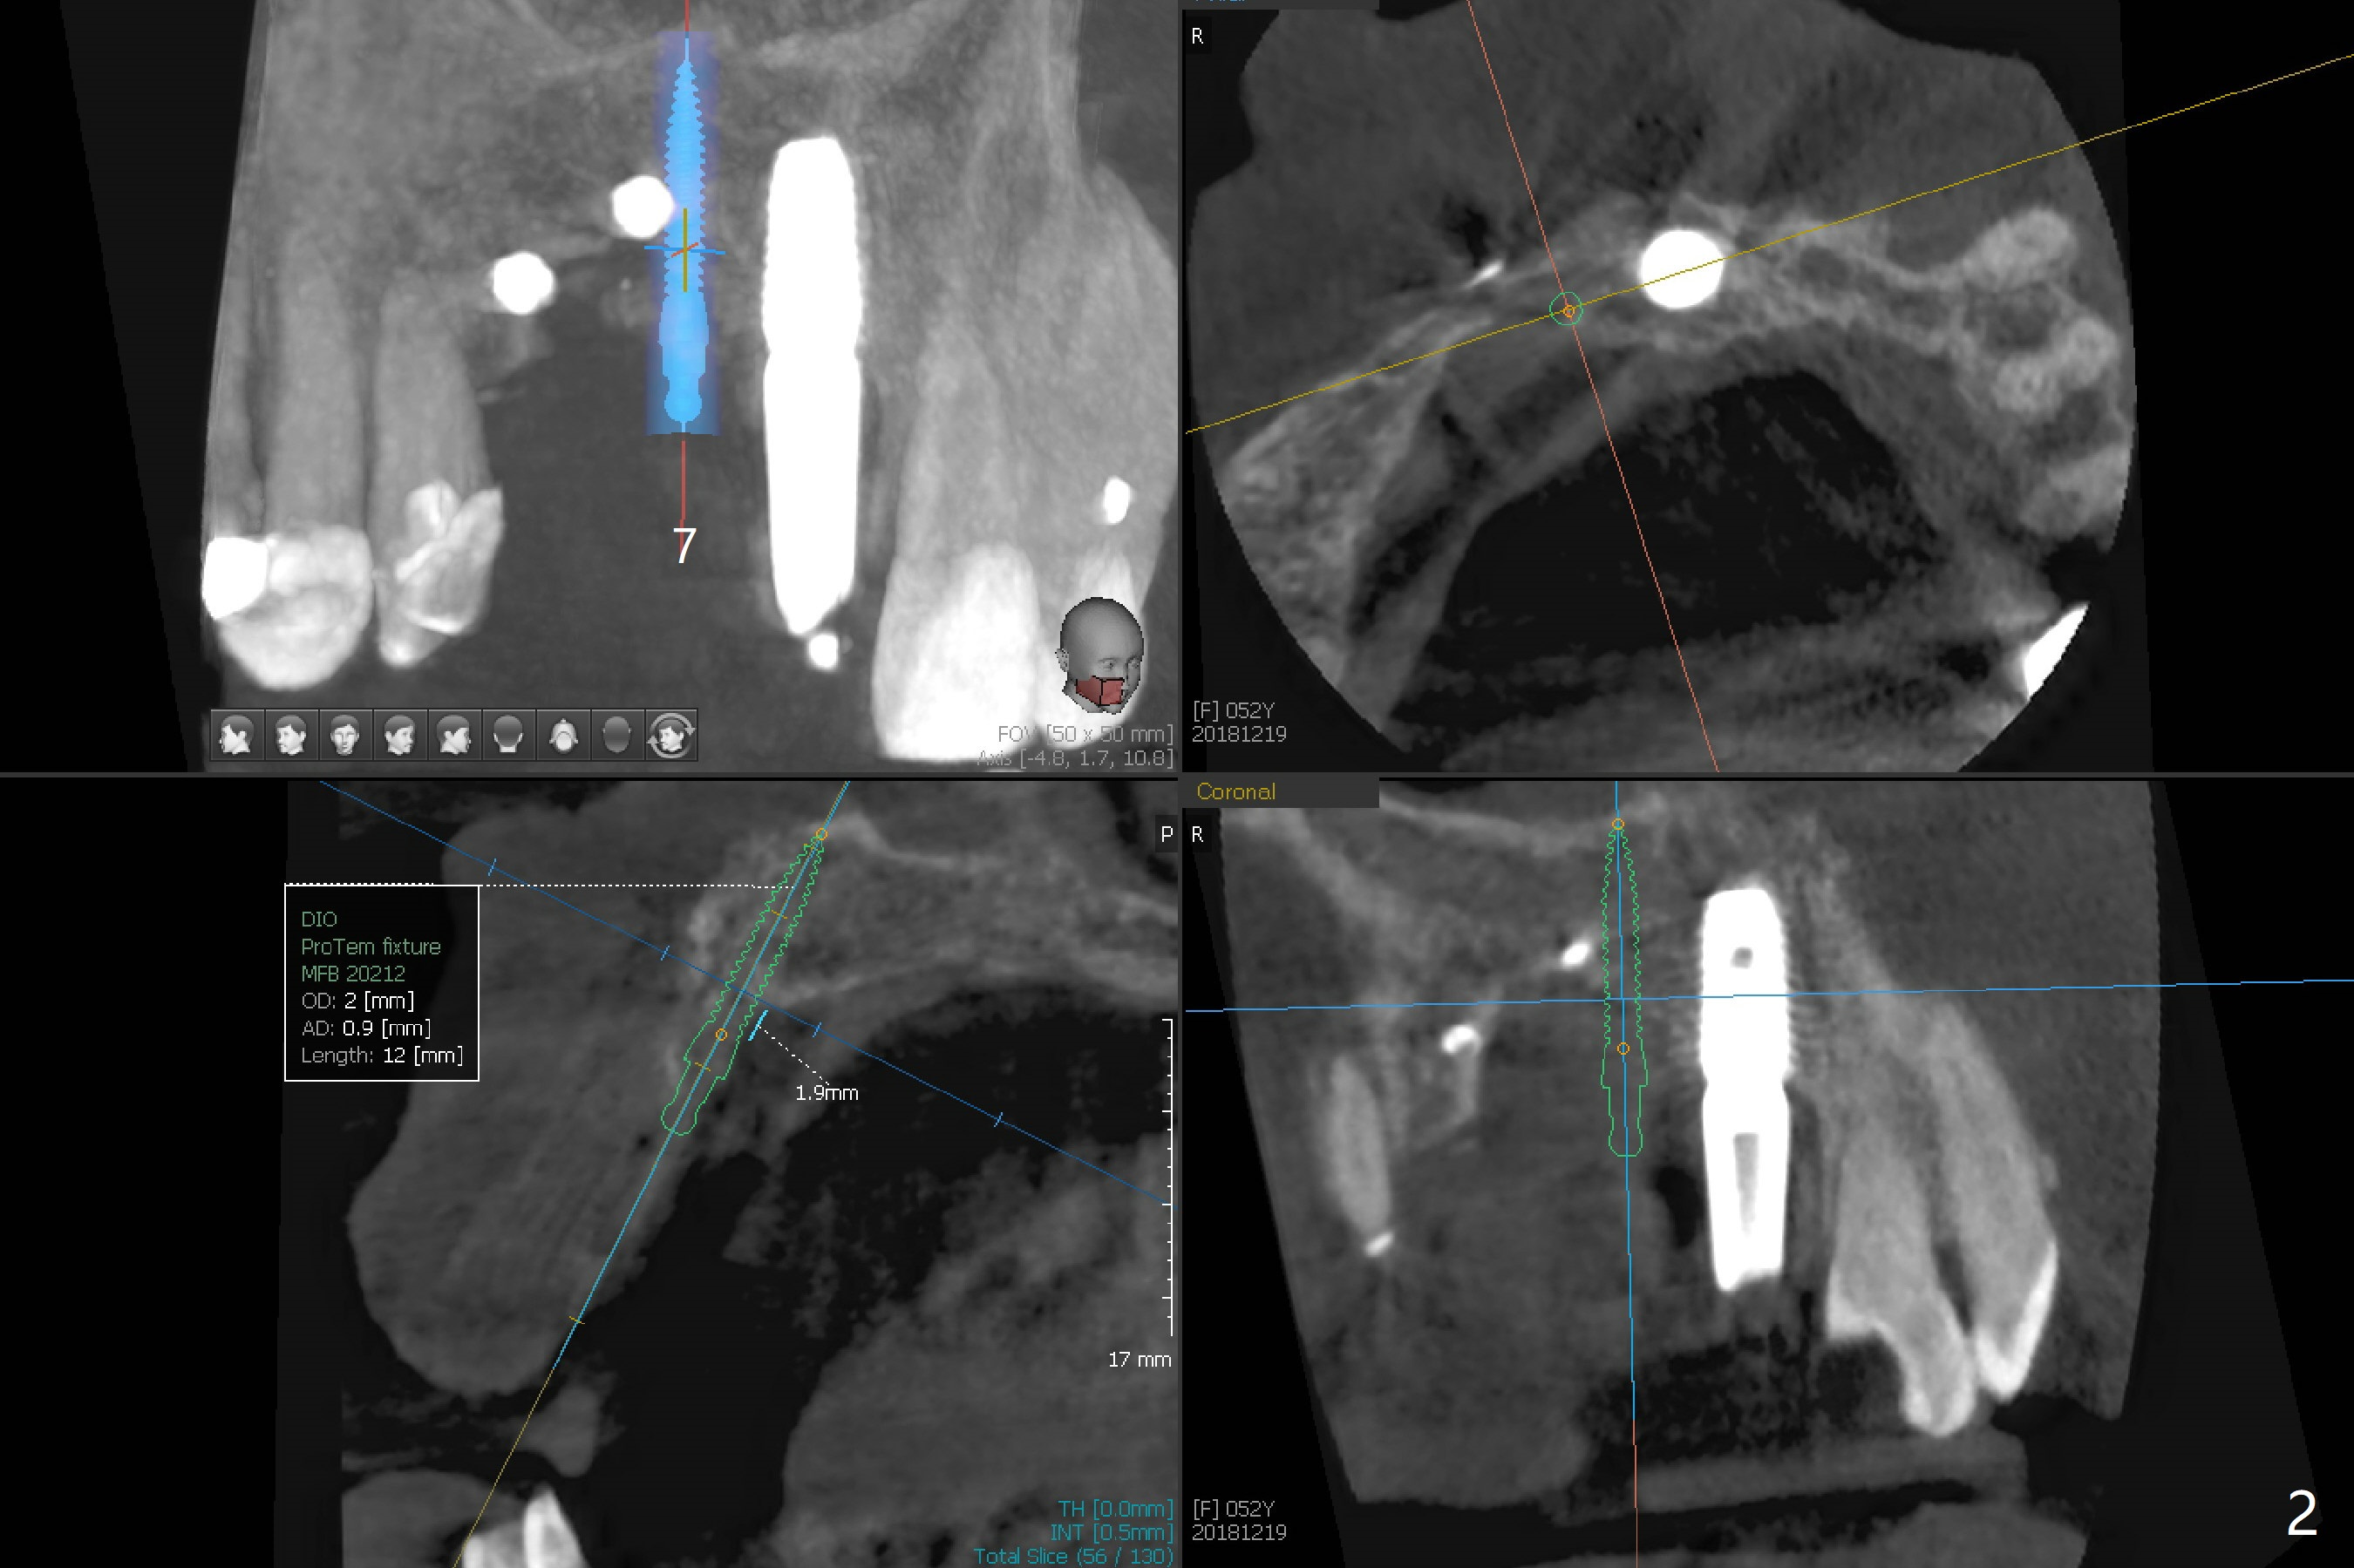

Four months post bone graft with tenting screws at #6 and 7 and implant re-placement at #8, the ridge at #6 and 7 appears to widen slightly, appropriate for narrow implants (Fig.1,2). Guide will be fabricated. The implant at #8 seems to have osteointegrated (Fig.3) with distal gingival recession (Fig.4). One year 5 months later, the tooth #5 is infected with apparently mesial bone loss (Fig.5 *) and papillary erythema and edema (Fig.6). However the pockets are not deep. A gingival embrasure is created between #5 and 6 for self cleansing. The latter does not work. Implants will be placed at #5 and 7 (Fig.7,8).